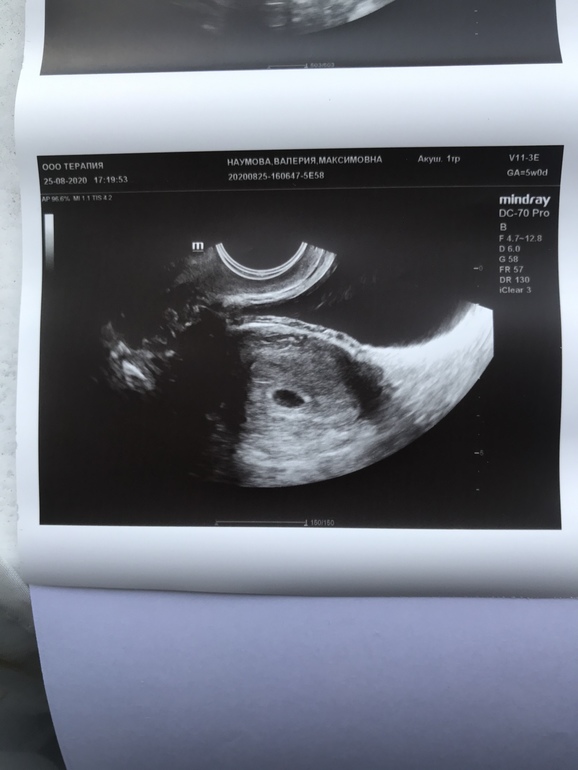

Срок по м ровно 5 недель По пя 5+3

У вас плодное яйцо всего 6 мм. Конечно, там еще ничего не видно 🤗 у меня в 5, 3 недель пя было 5мм и всё, через 1,5 недели уже и малыш 3,4мм, и жм 3мм, и чсс 106.

🤦🏼♀️🤦🏼♀️🤦🏼♀️ Боже какой бред ваш врач говорит. Вообще то могут заподозрить анэмбрионию если нет эмбриона в ПЯ больше 16мм, а подтвердить если его нет в ПЯ 25мм. У вас только 6мм ПЯ! Мне интересно какого размера эмбриона она там хотела найти? На сроке всего 5 недель. Девушка, у вас все в порядке, не переживайте, даже в 6 недель не всегда находят эмбрион. Переделайте узи в 7 полных недель, там уже точно все найдут)))